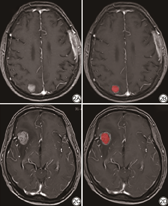

所有图像数据均从图片存档和通信系统(picture archiving communicating system, PACS)中读取,图像数据以DICOM格式保存,根据由一名初级放射科医师书写及具有高级职称的放射科医师审核的MRI诊断报告,应用ITK-SNAP软件(版本3.8.0,www.itksnap.org)在患者轴位增强后T1WI中进行勾画感兴趣区(region of interest, ROI),如图2所示。ROI勾画标准:(1)勾画边界为病灶内侧缘1~2 mm以内;(2)脑转移瘤病灶进行逐层逐个勾画;(3)尽可能避开周围水肿或其他组织。